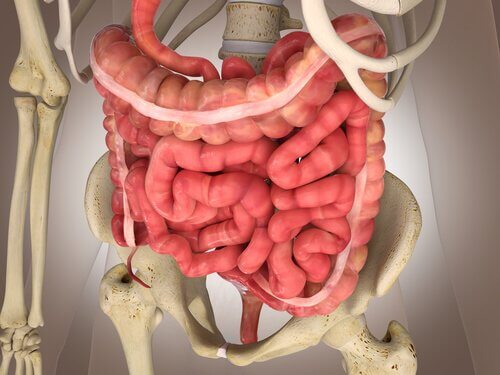

대장은 맹장, 결장, 직장 및 항문관을 포함하고 있다. 이들이 하나가 되어서 소화관에서 가장 넓지만 가장 짧은 부위가 형성된다. 오늘은 대장의 놀라운 생리학을 소개한다. 가장 먼저 신체의 중심부에 있는 대장은 수분과 전해질을 흡수하는 역할을 한다.

다음으로 중심부에서 멀리 떨어진 장은 대변이 배출되기 전까지 저장하는 역할을 한다. 이러한 기능에서는 결장의 움직임이 소장만큼 격렬하지 않아도 된다. 실제로 부드럽고 느린 움직임으로 수행된다. 그 결과 결장의 움직임은 소장의 움직임과 유사하다.